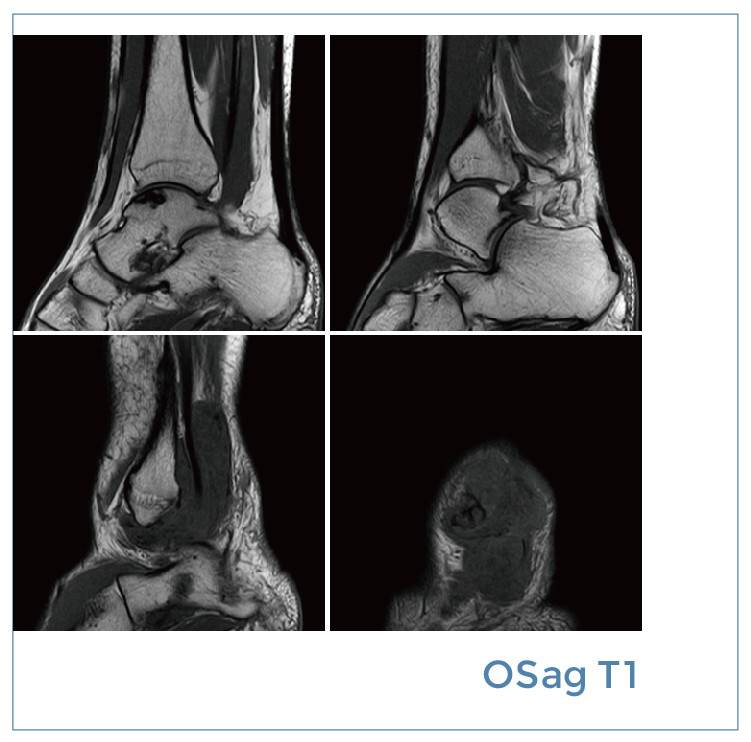

【朗润影像档案】磁共振影像病例分享(编号20191229)